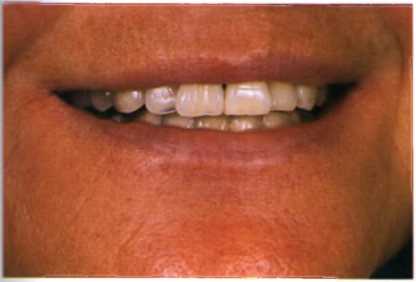

Улыбки в фотографиях: типы и комической моменты

Раздел: Фотогалерея мыслей